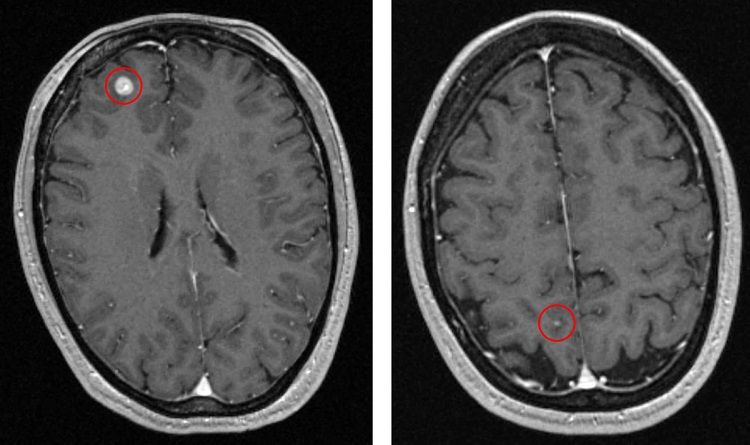

A 47-year-old female patient diagnosed with a right thigh melanoma underwent resection of the lesion in 2013 (Breslow depth 1.7 mm, Clark level IV, negative regional lymph nodes). She was diagnosed in 2016 with recurrent melanoma in the right thigh, inguinal nodes and left chest well. A staging MRI revealed two brain metastases (Figure 1); the patient reported no headaches and no neurological symptoms were detected.

The patient underwent Gamma Knife radiosurgery on September 16, 2016. The frame-based treatment was performed in a single session and entailed the delivery of 24 Gy to the 50% isodose line to lesion A (Figure 2, left image). Six isocenters were used: 5 x 4mm isocenters and a single 8mm isocenter. Lesion B (Figure 2, right image) received a total dose of 24Gy delivered to the 83% isodose line. A single 4mm isocenter was used.